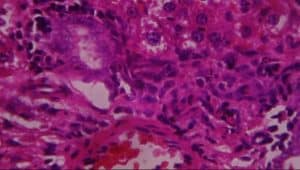

Figure 16: Rat given 400mg extract + lead acetate showing A-periportal infiltrates of inflammatory cells, B-vascular congestion, and C-patchy hepatocyte necrosis (H&E x 400)

On the contrary, evaluating the protective properties of aqueous extract of L. inermis by giving 400mg/kg of aqueous extract of L. inermis and thereafter inducing the injurious effect of 100mg/kg of lead acetate after 30 minutes was disastrous. This is to prove the fact that aqueous extract of L. inermis is useful in the treatment of already damaged liver cells rather than preventing. Clinically, this property of L.inermis could be taken into consideration in humans with similar liver lesions as confirmed histologically in this study: evidence-based anatomy.